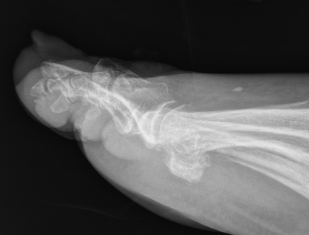

Interphalangeal joint dislocation

Pathology

Hyperdorsiflexion

P1 head dislocates plantar

Fractures

Xray

Blocks to closed reduction

Sesamoid interposition